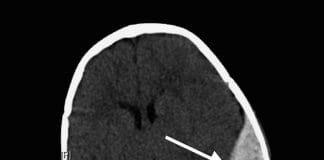

Subdural Kanama Akıl Kartı

Subdural hematomlar, dura ve araknoid membranlar arasında subdural aralıkta, köprü venlerinin yırtılması sonucu gelişen ve radyolojik olarak konkav (yarım ay) şeklindeki kanamalardır. Bazen %20-30...